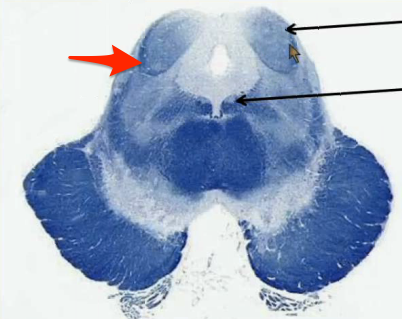

Where in the upper pons is the structure involved in focusing attention on stimuli and initiating sleep located?

Locus ceruleus in the dorsal part of the upper pons.

Where is the structure located in the brainstem that receives 2 point tactile discrimination and vibration sensation for the face?

Principal sensory nucleus in the dorsal middle pons.

Where is the structure located in the brainstem that innervates the muscles of mastication?

Motor nucleus of V in the dorsal middle pons.

Where is the structure located in the brainstem that innervates the lateral rectus muscle?

Abducens nucleus located in the dorsal lower pons, just anterior to the 4th ventricle. Note that its nerve goes through the tegmentum and basilar pons (inferior pontine sulcus) as it exits the brainstem.

Where is the structure located in the brainstem that innervates muscles of facial expression?

Facial nucleus, in the middle lower pons. Note that it slingshots its axons around the abducens nucleus before exiting the anterior lower pons.

Where is the structure located in the pons that receives pain, light tough and temperature signals from the face?

Spinal Vth nucleus and tract in the lower pons.